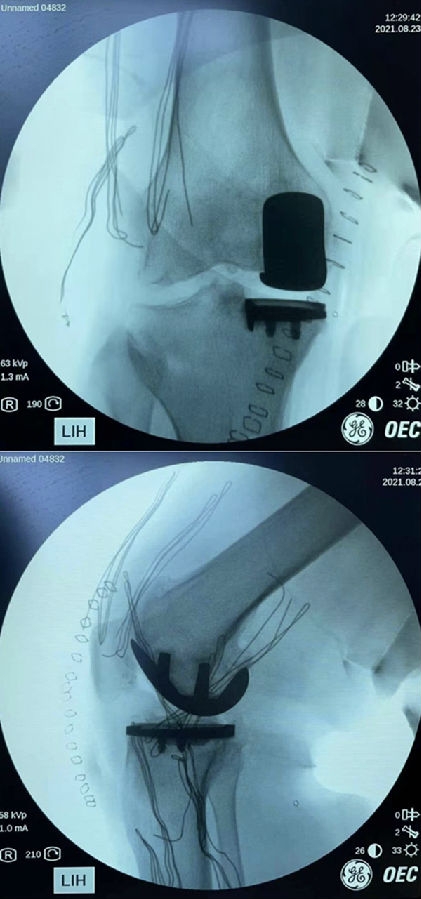

术后

本例患者术前内翻就比较重,术中恢复韧带原有张力后,仍刻意保持力线内翻,外侧间室保持2毫米减压松弛,从以往截骨经验来看,外侧这点软骨损伤,在关节内整体力学环境恢复到接近正常的情况下,对近期影响很小。远期生存率有待进一步观察。临床中对于这种膝内翻较重的患者,合并外侧软骨小剥脱,还是建议要综合力线、术前症状、年龄、身体状态等因素多方面考虑,对于体弱多病,高龄患者,为了减少创伤,仍倾向于单髁置换术。此时,力线控制就显得尤为重要,在恢复内副侧韧带张力的同时,要确保整体力线内翻,外侧处于减压状态,才能最大限度的降低外侧病变的影响。